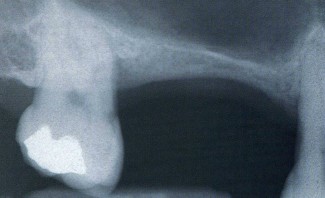

Questa tecnica viene eseguita qualora esista un ridottissimo volume di osso residuo in altezza nelle zone posteriori della mascella per poter posizionare degli impianti

In questa situazione occorre un aumento del volume osseo verticale mediante il grande rialzo del seno mascellare. Da un accesso operatorio intraorale il pavimento del seno è esposto e la membrana di rivestimento del seno è sollevata delicatamente.

Lo spazio formatosi viene riempito di osso autologo particolato e/o osso artificiale.

In presenza di uno spessore sufficiente di osso basale residuo (circa 4-5mm) gli impianti possono essere inseriti contemporaneamente al rialzo del seno mascellare. Altrimenti si rigenera dchirima l'osso e si procede al posizionamento degli impianti solo dopo un tempo di attesa di 6-8 mesi.